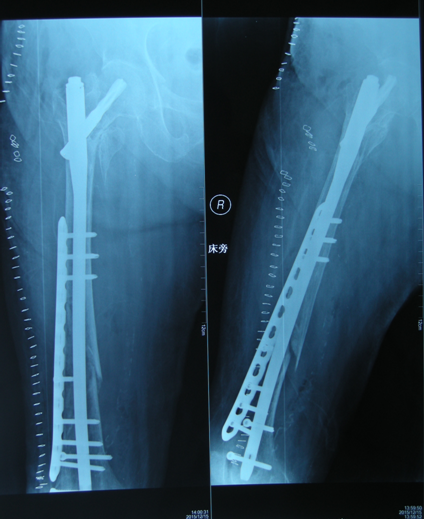

骨折术后再发骨折的手术治疗(骨科:刘菲)

患者老年女性,74岁,二次入院前5个月因外伤致右髋部疼痛,关节活动受限,拍片提示右股骨转子间粉碎性骨折,而入院行手术治疗,术后恢复良好。二次入院时因在家中洗澡时摔伤,拍片提示股骨干骨折,骨折部位位于内固定物远端。

明确诊断后,经过全科医生的术前讨论,详细制定了手术方案,再次给予手术治疗,将原有内固定物取出,换加长型PFNA,并用锁定钢板给予坚强固定,手术用时3小时,顺利完成。

术后常规治疗,由于坚强固定,术后早期功能练习,未出现明显并发症,恢复良好,患者及家属对于治疗效果很满意。